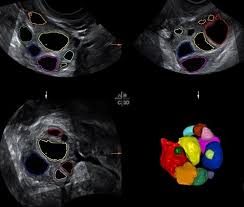

Wenn sie verdächtig aussehen Bauchwasser vorhanden ist oder Tumormarker im Blut sind muss man schnell operieren so der Gynäkologe. Da im Ultraschall eine Unterscheidung zwischen gutartiger Zyste und bösartigem Tumor schwer möglich ist werden Zysten nach dem fünfzigsten Lebensjahr meist operativ entfernt und untersucht. Ist das Gewebe bereits abgestorben muss der Eierstock entfernt werden.

Welcher Weg gewählt wird ist abhängig von der Art der Zyste den klinischen Symptomen der Länge des Bestehens der Eierstockzysten und vom Alter der Patientin Der Arzt wird dann zu einer operativen Bauchspiegelung raten wenn gutartige Geschwüre wie Gebärmutterknoten Myome oder Zysten an den Eierstöcken Beschwerden bereiten und klein genug sind um mittels Bauchspiegelung entfernt zu werden. Das Gleiche gilt wenn eine Veränderung im fortgeschrittenen Alter entdeckt wird. Lediglich im Falle von Komplikationen kommen Patientinnen nicht immer um einen Eingriff herum.

Nach 6-8 Wochen wird durch den Ultraschall. Diese bilden sich nämlich aus dem Follikelrest nach dem Eisprung.